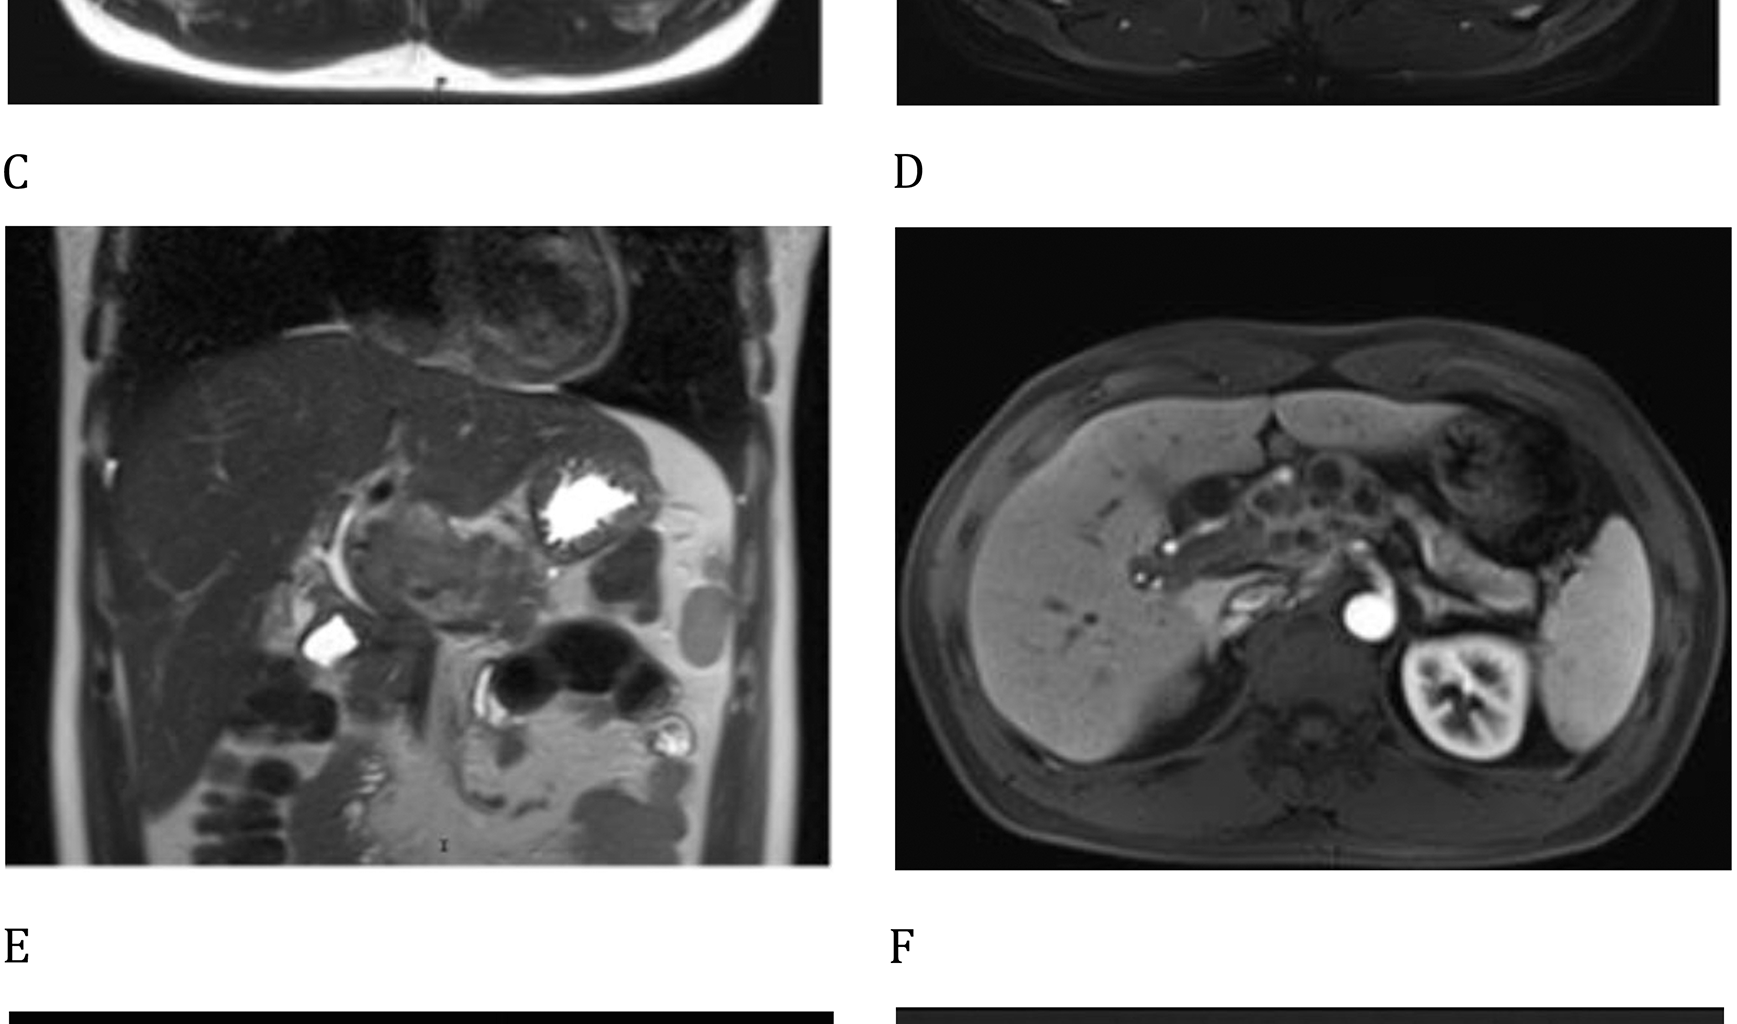

Tuberculous granulomas, the common form of tuberculous lesions, are typically composed of centrally located activated macrophages harboring tuberculosis bacteria, surrounded by peripheral lymphocytes and fibroblasts. After enhanced MRI analysis, the peripheral enhancement seen in these lesions highlights the distinct arterial blood supply to tuberculous granulomas, providing a theoretical basis for the use of RAI. Isoniazid is the first-line drug for the treatment of tuberculosis and is effective in managing both active tuberculosis and latent infections [6]. It is often used as a monotherapy or in combination with other agents. Isoniazid exhibits selective antibacterial activity against Mycobacterium species, likely due to its ability to inhibit the synthesis of mycolic acid, which is essential for the formation of the bacterial cell wall.

Pancreatic tuberculosis can occur in all anatomical regions of the pancreas, including the head and tail, with the pancreatic head being the most frequently involved site [13]. The lesions typically manifest as solid masses or cystic formations, often demonstrating radiographic calcifications. These pathological changes may cause compression or obstruction of adjacent vascular structures, including the portal vein, superior mesenteric vein, and hepatic artery [14]. During the initial imaging diagnosis, differential diagnosis between pancreatic tuberculosis and pancreatic cystic neoplasms must be carefully considered [15]. The laboratory indicators of pancreatic tuberculosis exhibit limited specificity. As an infectious pathology, pancreatic tuberculosis typically presents with an elevated erythrocyte sedimentation rate (ESR) and variations in blood parameters, which are potential markers for initially differentiating between pancreatic lesions and neoplastic processes. Pancreatic tuberculosis may also show elevated levels of tumor markers such as CA125 and CA199 [16, 17], as well as increased AFP levels, which could lead to a misdiagnosis as pancreatic cancer. The rise in CA199 levels has been linked to potential associations with pancreatic head masses and gallbladder obstruction caused by enlarged lymph nodes.